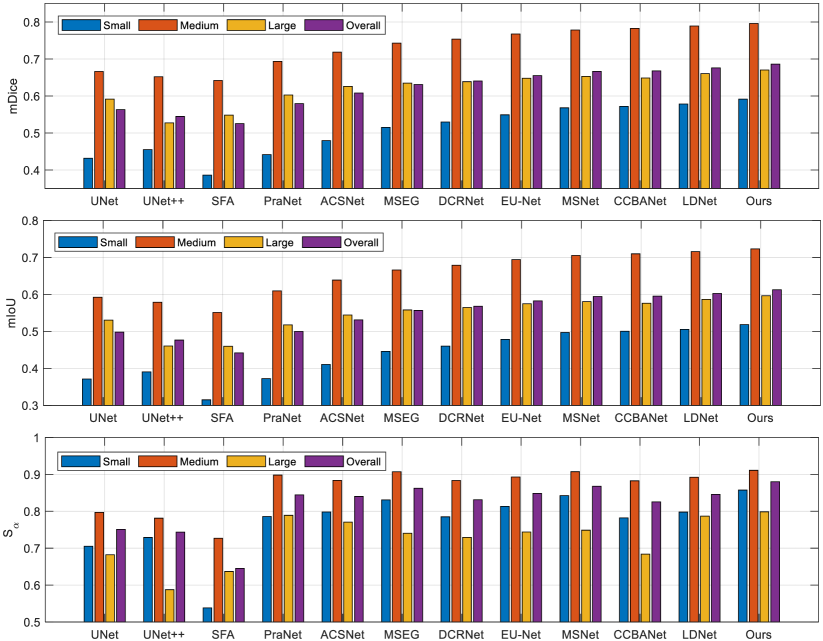

Scale variation is one of the most challenging factors in the polyp segmentation task. In this study, we have proposed to fully learn the scale-aware features and effectively fuse the cross-level features to enhance the discriminative ability of the learned features, which are helpful in dealing with scale variation. Thus, we conduct a scale-based evaluation for different methods. In this study, we calculate a ratio () involving the size of the polyp area into a given image to characterize the scale of the polyp region. To achieve this, three types of polyp scale are defined,i.e., 1) When , the polyp is regarded as “small” type; 2) When , it is regarded as “large” type; and 3) When the ratio is in the range of , we call it as “medium” type. Further, we collect a hybrid dataset derived from the five used colonoscopy datasets (testing images), where , , and of images are with the three types, respectively. Fig. 7 presents the comparison results of the attribute-based study w.r.t. polyp scale in terms of three metrics (i.e., mDice, mIoU, and ). Based on the results, we have the following observations: 1) our proposed method obtains better performance over other compared methods under these conditions of different polyp scales, and 2) our model and all comparison methods achieve better performance in segmenting “medium” polyps while they obtain relatively lower performance in segmenting other types. This suggests that scale variation is still a challenge for polyp segmentation, and it is relatively easy to segment the “medium” polyps.